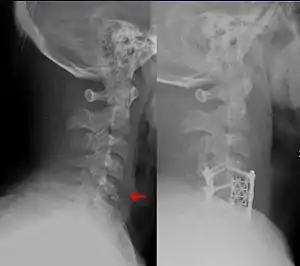

This fracture of the lower cervical vertebrae is one of the conditions treated by orthopedic surgeons and neurosurgeons.